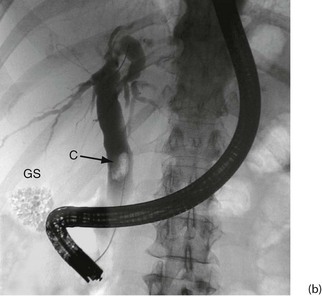

Fig. 5.6 Some techniques for demonstrating the biliary system

(a) and (b) Endoscopic retrograde cholangiography

The patient is sedated and a side-viewing gastroscope passed down so the tip reaches the second part of the duodenum. The ampulla of Vater is cannulated under direct vision and contrast medium injected to outline the bile ducts. (b) A large gallstone C is seen within the dilated common bile duct and a collection of radiopaque gallstones GS is seen in the gall bladder

Endoscopic retrograde cholangio-pancreatography (ERCP): This is described below (see Diagnostic and therapeutic duodenoscopy); its use in obstructive jaundice is described in detail in Chapter 18. The basic technique is illustrated in Figure 5.6 a and b.